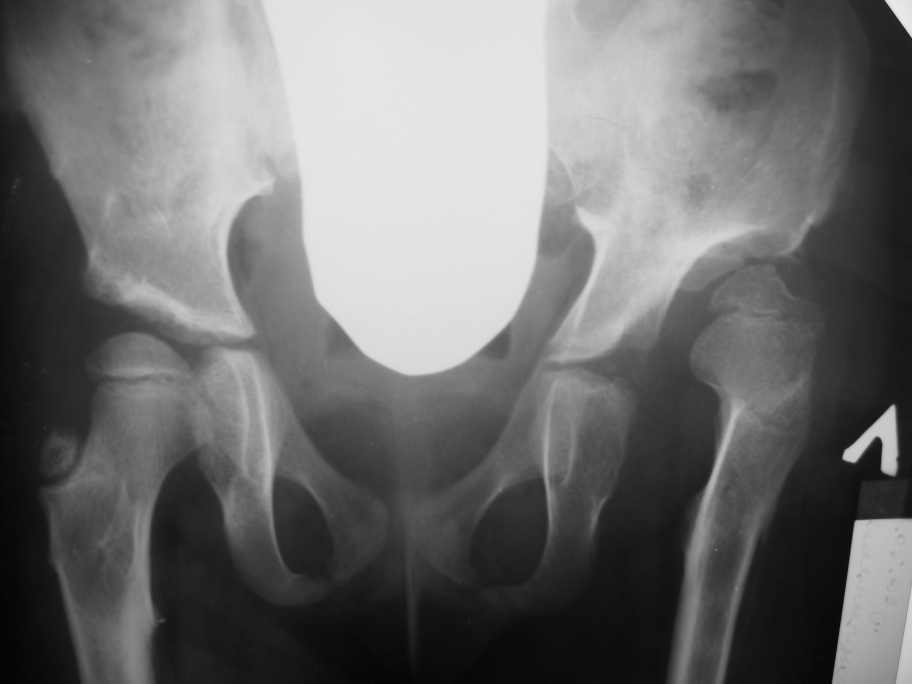

Уважаемой Ihor! Следует дообследовать ребенка, проведя РКТ или МРТ. Необходимо установить взаимоотношение головки бедренной кости и вертлужной впадины слева, оценить угол антеторсии и истинный ШДУ. Далее решать вопрос об оперативном лечении. Скорее всего показана деторсионно-варизирующая остеотомия в межвертельной области левого бедра и остеотомия таза типа Солтера (хотя ацетабулярный индекс великоват, т.е. более 30-35 градусов). Справа следует понаблюдать и периодически проводить курсы ФТО и ЛФК. Если Вы не имеете опыта реконструктивной хирургии ТБС у детей, то лучше отправить пациента к детским ортопедам. АИФ